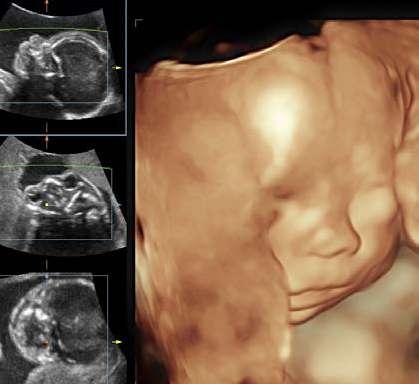

La idea de realizar ultrasonido 3D en obstetricia nació con el objetivo de visualizar estructuras anatómicas. El Dr. Tanaka a principios de 1980 quiso reconstruir y visualizar planos sagitales y coronales a partir de imágenes adquiridas en plano transversal, permitiendo ratificar la ubicación y expansión de la placenta, así como también observar con mayor claridad al feto.

La utilidad o incorporación de la ecografía 3D en la práctica clínica va más allá de un tema visual de imágenes atractivas. En obstetricia se han propuesto beneficios potenciales de la ecografía en 3D, que incluyen: (1) la capacidad de revisar datos volumétricos interactivamente, (2) la posibilidad de utilizar diferentes planos de sección para evaluar estructuras anatómicas, (3) la posibilidad de rotar la imagen volumétrica para examinarse desde diferentes perspectivas, (4) la precisión

La ecografía en 3D ha sido utilizada desde principios de la implementación de la ecografía diagnóstica. El proceso de convertir imágenes 2D en 3D o 4D (3D en movimiento o también llamada 3D en tiempo real)”

La ecografía 3D y 4D para la valoración de la cara fetal cada vez interesa más detectar alteraciones como el labio, paladar hendido, y algunas malformaciones faciales relacionadas con fenotipos de trastornos genéticos subyacentes. Algunos autores han utilizado imágenes en 3D de rostros fetales para identificar de forma temprana alteraciones genéticas analizando la mandíbula, el hueso frontal y la nariz. Así mismo, se documentó que los movimientos fetales y las expresiones de la cara presentaban correlación con la actividad cerebral fetal y su estado de desarrollo (parpadear, morder la boca, sonreír y bostezar).